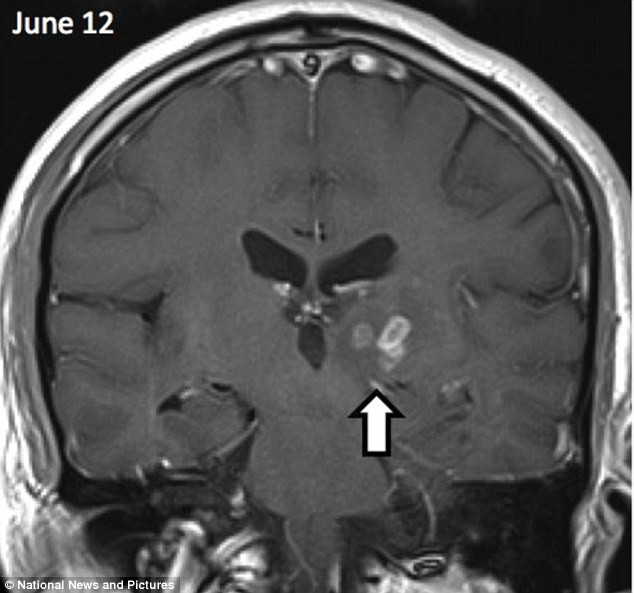

Rất may mắn, các bác sĩ đã tiến hành gắp bỏ thành công con sán này ra khỏi não của bệnh nhân và ông đang hồi phục tốt sau ca phẫu thuật loại bỏ sán.

| Con sán dài 5cm di chuyển từ bán cầu não phải sang bán cầu não trái của người đàn ông (Ảnh: Dailymail) |

Theo phân tích, con vật ký sinh này lành tính hơn trong số 2 loại sán sparganosis đã biết. Loài sparganosis nguy hiểm hơn có thể đẻ trứng với số lượng rất lớn, sau đó ăn hết não bộ của người khi chúng lớn lên.

Tuy nhiên, loài sán này có bộ gen đặc biệt, chúng có khả năng kháng với các thuốc chống sán dây hiện tại. Điều này đặt ra lo ngại về nguy cơ tăng nhiễm sán khi có rất nhiều người thích đi du lịch ở những địa điểm mới lạ, ít người biết đến.